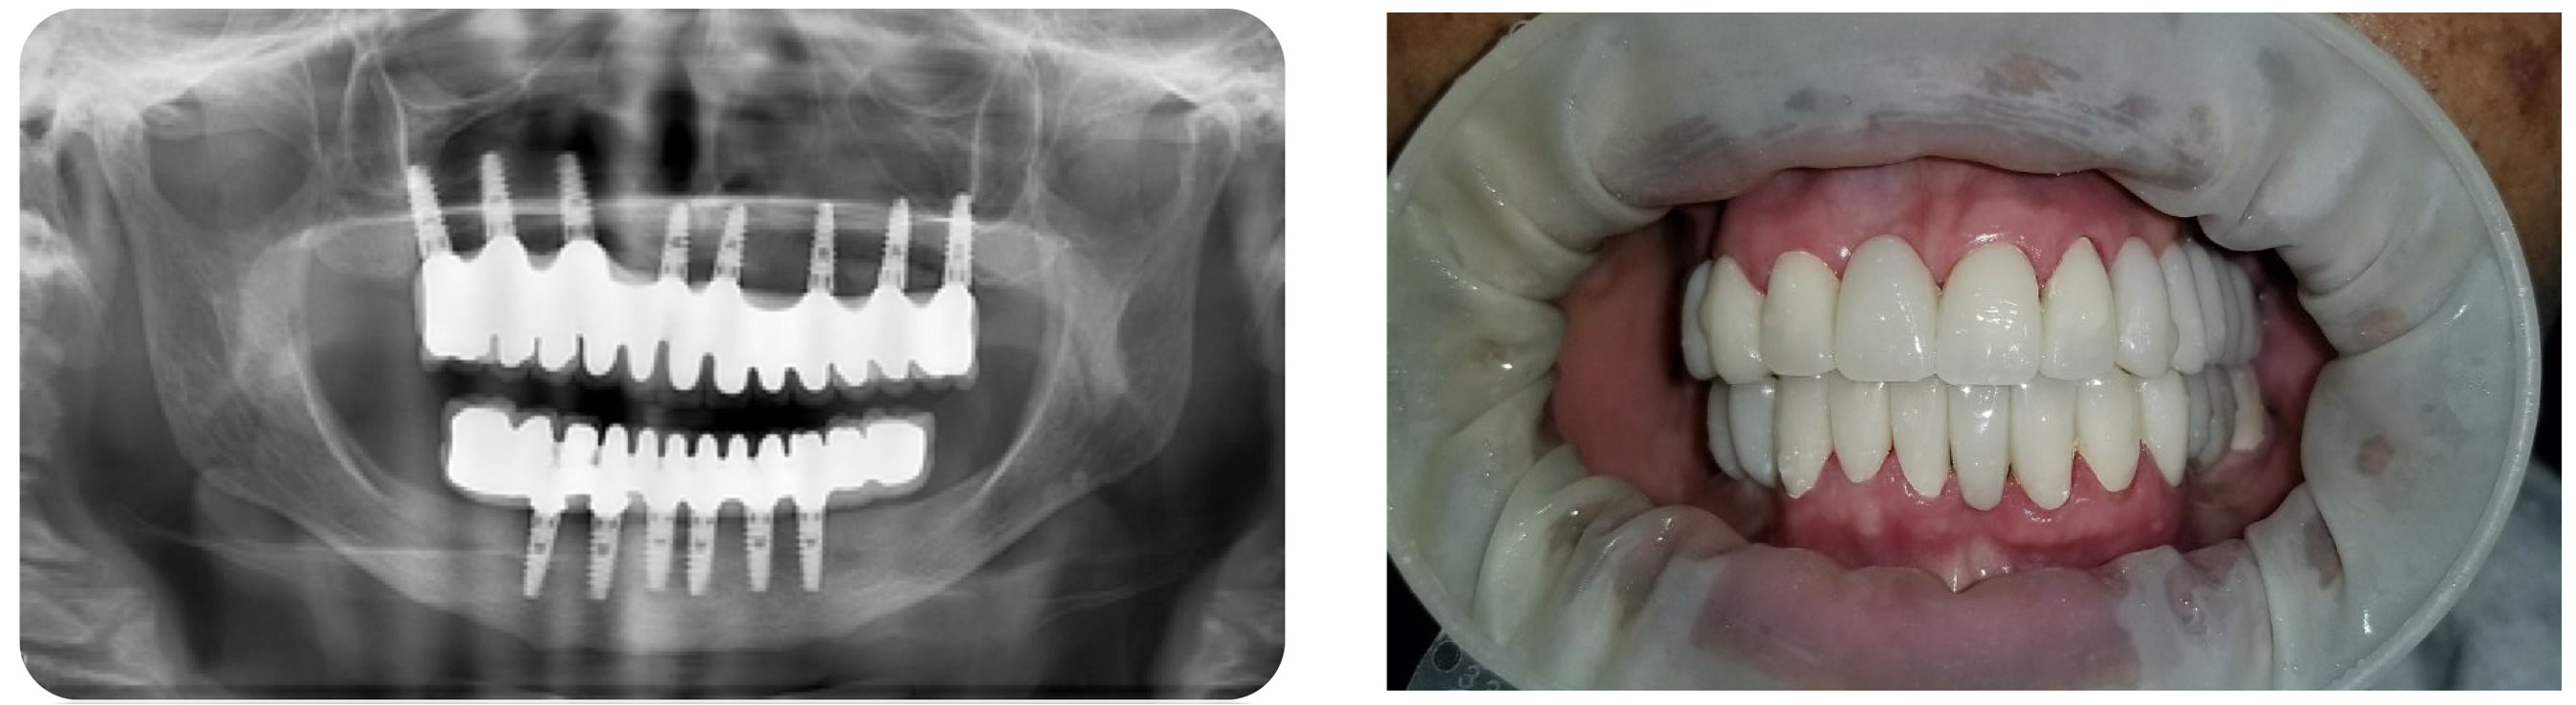

Los implantes son elementos metálicos usualmente en titanio puro que se ubican quirúrgicamente en los huesos maxilares, debajo de las encías. Una vez colocados en el lugar se puede colocar sobre ellos las coronas o puentes fijos que reemplazarán a las piezas dentarias perdidas